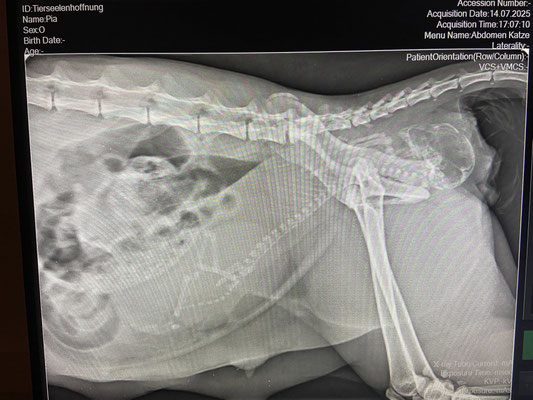

Wenn Tierhilfe zur Tierqual wird – Lebensgefahr für Hope

!!So wie bei Hope, einer jungen Katze, die trächtig bei tierlieben Menschen aufgenommen wurde.

Hope brachte zunächst zwei gesunde Kitten zur Welt. Doch zwei Tage später folgten zwei Totgeburten, da sollten schon die Alarmglocken schrillen. Am dritten Tag bekam sie erneut Wehen – Alarmstufe Rot: Ein totes, bereits aufgedunsenes Kitten blockierte den Geburtsweg. Lebensgefahr für die Katzenmutter!

Notkaiserschnitt in der Tierarztpraxis Vöcklamarktwir danken von Herzen, dass Hope sofort operiert wurde.

Sie lebt! Was gut gemeint war, hat für 3 Kitten tragisch geendet. RIP kleine ENGELN!